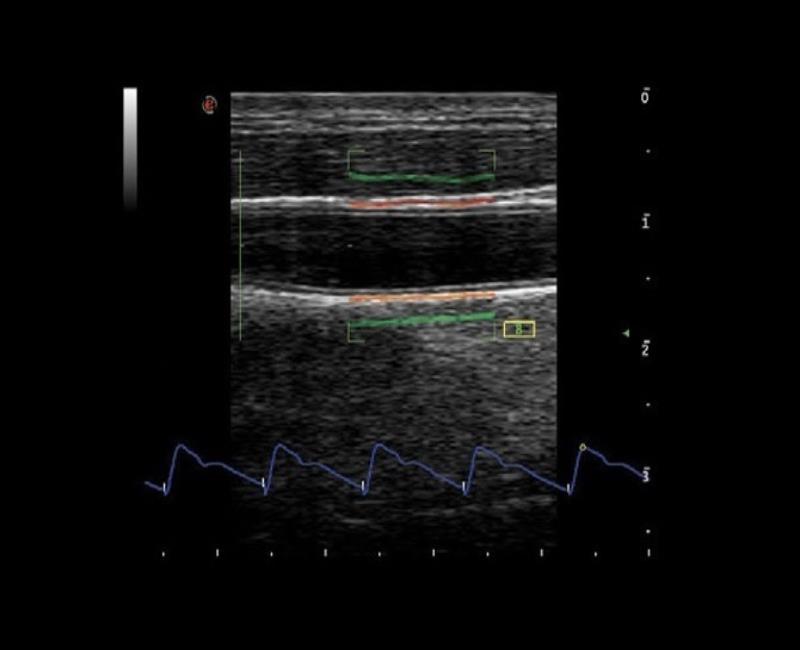

Siêu âm tim mạch

TVM: bản đồ vận tốc mô với chế độ kép (Doppler màu và Doppler năng lượng).

Sóng RF: Công nghệ đo độ đàn hồi thành mạch máu bằng sóng RF (Radio Frequency) giúp tiên lượng nguy cơ xơ vữa động mạch và đột quỵ.

Tài liệu: Brochure mylab X7